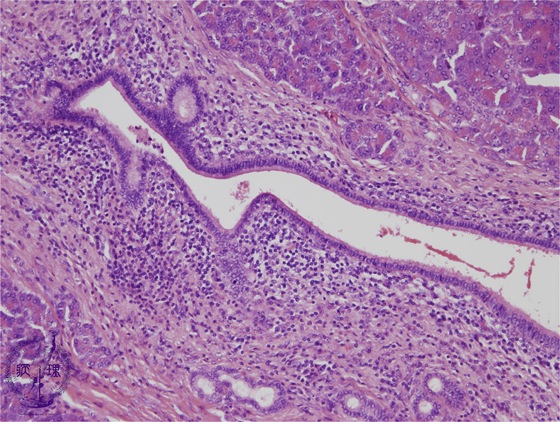

Microscopic findings(HE stain, mid-power):There is marked fibrosis and lymphocytic inflammation around the interlobular pancreatic duct.